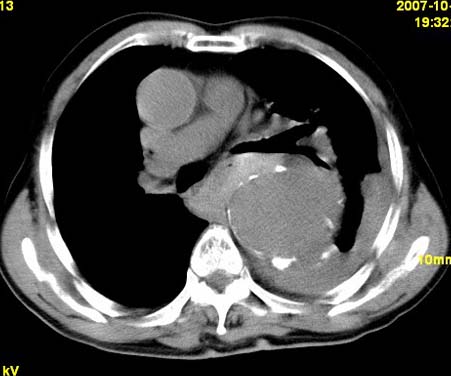

标题: CT10190:男,70,胸部疼痛数年,加重一天。典型病例。 [打印本页]

标题: CT10190:男,70,胸部疼痛数年,加重一天。典型病例。

典型降主动脉瘤伴血栓形成.瘤体下部局部边缘不清,结合病史,不除外局部撕裂外渗可能.另左侧胸水,肺部压迫不张改变.建议增强进一步检查.

1.降主动脉瘤伴血栓形成.2.左侧胸腔积液,考虑为主动脉瘤破裂所致。

降主动脉明显增粗,边缘模糊,周围低密度影,双侧胸膜腔少量积液,结合临床考虑胸主动脉瘤破裂并双侧胸腔积液。